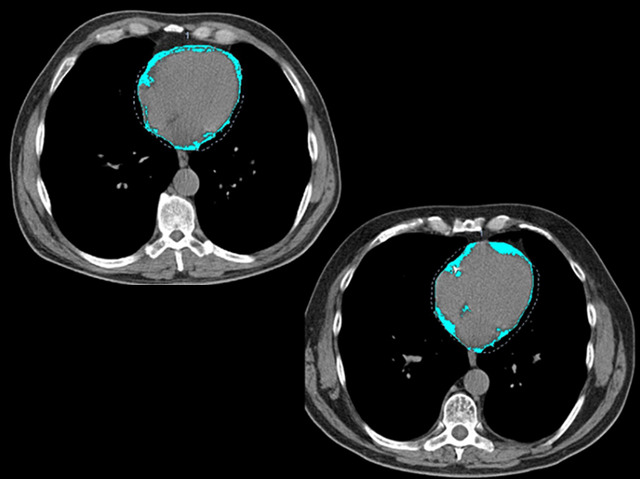

Over three million people in the UK are living with the debilitating lung condition COPD (chronic obstructive pulmonary disease). Many sufferers also develop cardiovascular disease and the combination can be fatal. A test to identify which COPD patients are at high risk of heart disease would allow doctors to tailor treatments more effectively. The answer may be to use CT scans to measure the volume of a type of fat, epicardial adipose tissue (EAT), around the heart. Increased EAT is clearly linked to cardiovascular disease. These CT scans show a chest cross-section for two men, both ex-smokers of a similar age and weight, but one has COPD (bottom) and the other doesn’t (top). The man with COPD has 30% more fat (pale blue) around his heart, and therefore a higher risk of heart disease.